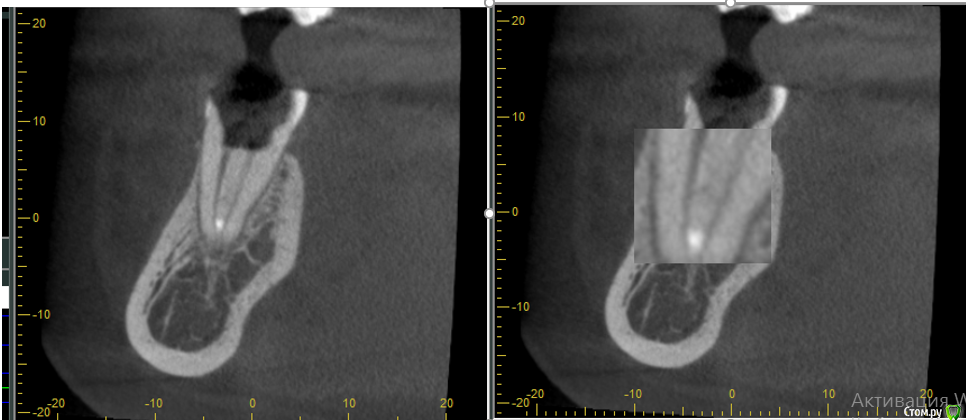

Mashelya Опубликовано 14 апреля, 2016 Поделиться Опубликовано 14 апреля, 2016 Всем добрый день! Пациентка 33 года. Пришла ко мне в ноябре 2015. Беременность 32 недели. Болит зуб 36. Снимок 1. Ноющая боль усиливается при накусывании. Перкуссия 36 положительная. Сделали снимок- штифт в дистальном канале. Расширение периодонтальной щели. Ну что делать- зуб болит, распломбировали, помыли почистили. Отделяемого не было. Два раза она ко мне приходила с интервалом 2недели. Мыли и каласепт. Договорились долечить после родов. Она больше не приходила, не звонила. Приходит ко мне дней 10 назад. Снимок 2. Говорит, за 2дня до этого скололась временная пломба, и, так как ко мне ехать далеко, а дома маленький ребенок, сходила в ближайшую стоматологию с целью поменять пломбу. Там ей естественно все вскрыли, снова чистили, мыли каналы. И вот теперь снова все болит. Ну в каналах, к слову, ничего не было(пасты имею в виду), ни на снимке, ни визуально. Снова все моем. Оставляю каласепт. Пациентка говорит, что прям вот уже все прошло, ничего не болит, уже жаждит вкладку и коронку. Я предлагаю сделать КЛКТ, так как в принципе вижу зуб в третий раз и то через полгода. И вот что видим. На медиальном корне большой воспалительный процесс. Дистальный тоже не в порядке. Перелечивание с вкладкой и коронкой примерно 25 т.р. Как считаете, это перспективно? Ведь процесс не на верхушке а между корнями, вот что меня смущает. Не хочу обнадежить человека, если потом все равно имплантация через пару лет. Ссылка на комментарий

Mashelya Опубликовано 15 апреля, 2016 Автор Поделиться Опубликовано 15 апреля, 2016 Обговорить все с пациенткой и лечить. Финансы это вопрос субъективный. Процесс у медиального корня виден на снимке до лечения. Каналы расширены были слабо, соответственно перфо или трещины там быть не должно. Широкая латераль, да. Так что мыть, мыть, мыть и паковать. Смотрите, это не может быть трещиной? Или как раз латераль? Ссылка на комментарий

DmitrySH Опубликовано 15 апреля, 2016 Поделиться Опубликовано 15 апреля, 2016 Больше похоже на анастомоз между каналами. 3 Ссылка на комментарий

Л Ю С Я Опубликовано 15 апреля, 2016 Поделиться Опубликовано 15 апреля, 2016 Отличное качество КЛКТ . +1 к анастомозу и латеральке. Пакуйте плотно, герметичная реставрация, через 6 мес ещё раз кт. Если пациентка не хочет и др причины, удаляйте. При правильном соблюдении протокола 80 % успеха. Если конечно от кор части что то осталось. Трещины обычно не так выглядят 1 Ссылка на комментарий

DmitrySH Опубликовано 15 апреля, 2016 Поделиться Опубликовано 15 апреля, 2016 Там если присмотреться, то возможно щелевидное подобие ММ канала. Но если в полости не удается зацепиться, то очень хорошо все мыть надо. Ссылка на комментарий